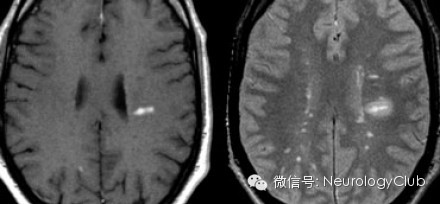

第二方面:T1像上显示的黑洞black holes)

1、代表脑实质局灶损伤区域

2、可能反映急性水肿性病变或基质破坏伴轴索丢失

3、一般不强化;水肿性黑洞起初强化,时间久后不强化